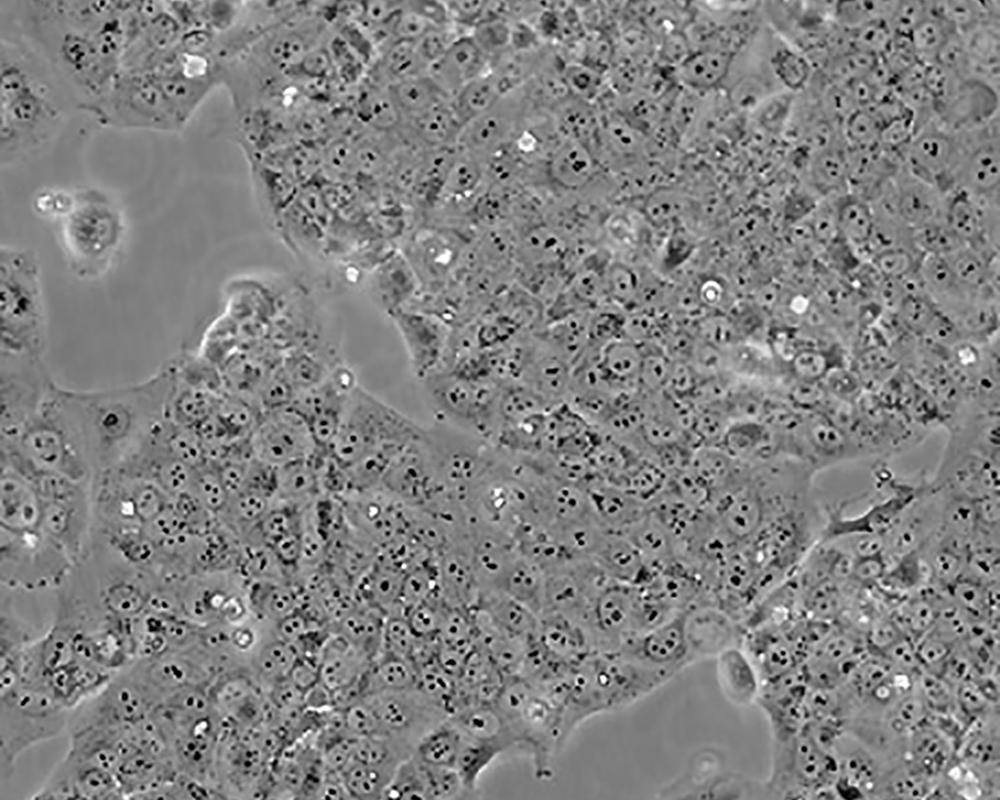

JEG-3

產品名稱 JEG-3

中文名稱 人絨毛膜癌細胞

組織來源 妊娠性絨毛膜癌;腦轉移;女性

生長特性 adherent

形態特征 epithelial

細胞描述 T這是一株超三倍體人類細胞株